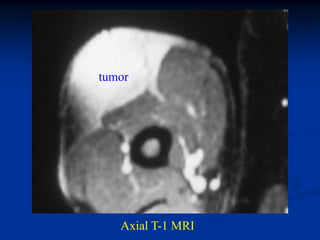

Case #1205

38 year female with

hemangioma forearm

with hypertrophic response

in subadjacent ulna

Bone scan

bone

hypertrophy

Axial PD MRI

Axial gad contrast MRI

Sagittal T-2 MRI

Case #1205 38 yearfemale with hemangioma forearm with hypertrophic response in subadjacent ulna